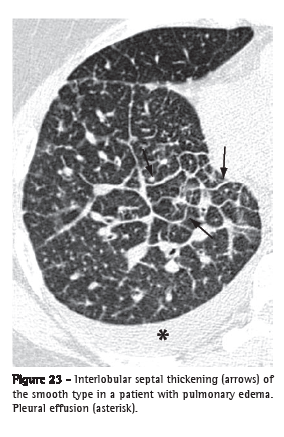

Interlobular septal thickening (espessamento de septos interlobulares)

Interlobular septal thickening is the thickening of the connective tissue septa separating the secondary pulmonary lobules. It is radiographically characterized by thin linear opacities, also designated Kerley B lines. It is usually in close contact with the lateral pleural surface, near the costophrenic sulci, at a right angle to the pleural wall. Currently, the terms "septal lines" or "septal thickening" have gained favor over Kerley lines. On HRCT scans (Figure 23), the thickening of the interlobular septa is characterized by the presence of linear opacities that delimit the secondary pulmonary lobules, more easily characterized in the subpleural region, in which it has the aspect of lines at right angles to the pleural surface.(3,44) In the central regions of the lungs, the thickening of the septa of adjacent lobules results in the aspect of polygonal arches. Septal thickening can be secondary to changes in any of its components (veins, lymphatic vessels or connective tissue) and is a finding common to various lung alterations; however, its presence is particularly highlighted in cases of pulmonary edema and lymphangitic carcinomatosis. Septal thickening can be smooth (Figure 23), nodular (Figure 24) or irregular. This differentiation can aid in the differential diagnosis.

The secondary pulmonary lobule is the smallest anatomic unit of lung delimited by a septum of connective tissue. It is polyhedral in shape, measures 1.0-2.5 cm in diameter and contains a variable number of acini.(45) The center of the lobule is formed by the bronchiole and its accompanying pulmonary artery, lymphatic vessels and adjacent interstitium. In its periphery, the connective tissue forms thin septa designated interlobular septa, which contain small pulmonary veins and lymphatic vessels (Figure 25). In normal patients, the interlobular septa are better identified in the anterior, lateral and paramediastinal peripheral regions of the upper and middle lobes, as well as in the peripheral region of the anterior diaphragmatic region of the lower lobes, tending to be incomplete or absent in the remaining lung regions. The interlobular septa are easily recognized on HRCT scans when the septal interstitium is affected (Figures 23 and 24).(3)